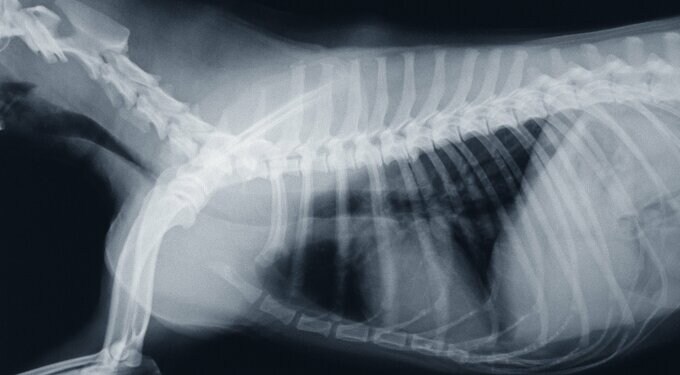

犬が「抜歯手術」を受けた。本当にがんばった…ある長い1日のこと 記事に戻る スクロールで次の画像 (画像 1/6) この記事を読む 2025/01/20 (画像 2/6) この記事を読む (画像 3/6) この記事を読む 母が家族に送った写真 (画像 4/6) この記事を読む (画像 5/6) この記事を読む (画像 6/6) この記事を読む